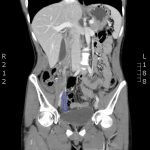

The CT abdomen/pelvis with intravenous contrast shows a dilated appendix (see red outline) with thickened, hyperenhancing wall (see blue outline) best visualized in the axial and coronal planes.